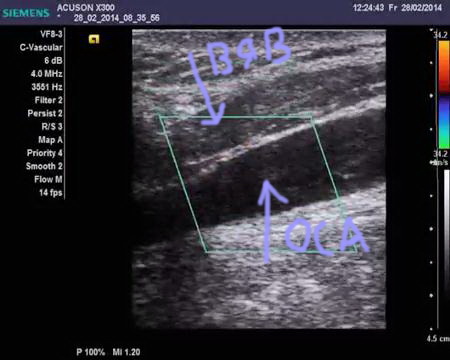

Яремная вена на узи

Яремная вена на узи 106 фото